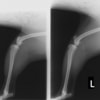

■ 症例20 ポメラニアン 8ヶ月 1.8kg

左右膝蓋骨脱臼 グレードⅢ

2ヶ月前から間欠的跛行が認められ、両膝の膝蓋骨脱臼整復術を行った。

手技は縫工筋及び内側広筋の解放、脛骨粗面の外側転位、滑車ブロック形造溝術、内外側関節包の縫縮を選択し実施した。

右側の膝蓋骨脱臼は上記手技で整復されたものの、左側はそれのみでは膝蓋骨が浮く様子が認められた。その為、PDS縫合糸にて膝蓋靱帯を1糸のみ縫合し、靱帯の縫縮を行った。